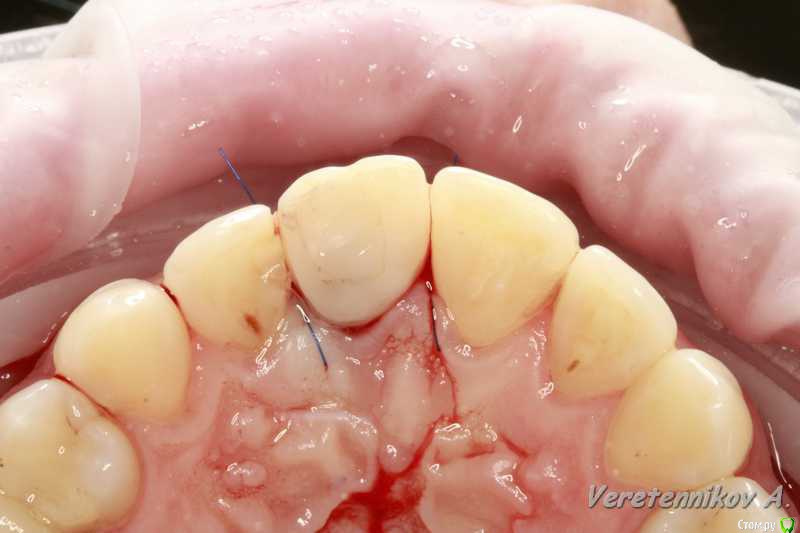

an_ver Опубликовано 15 декабря, 2015 Поделиться Опубликовано 15 декабря, 2015 Травма 21, немного сместился,удаление,имплантация SPI 4.2*13,ГенОсс+ ауто со сверла,для временной коронки использован свой зуб)),немного укоротили реж.край,чтоб не травмировать,унифлекс 5/0 18 Ссылка на комментарий

an_ver Опубликовано 17 декабря, 2015 Автор Поделиться Опубликовано 17 декабря, 2015 Перед имплантацией снимаете слепок,в слепок втыкаете бор от прямого,слепок промазываете изолятном,у меня гламур))) водорастворимая из интим магазина,заливаете Люксатемп,достаете,расширяете отверстие от бора,для вр.абатмента,затем базой от слепочного,делаете модель со слепка,ставите туда зуб,жидкотекучим его соединяете с режущими\жевательными поверхностями и вот готов шаблон,потом отрезаете крылышки эти и вот вам временная коронка на абатменте.Можно проще сделать,если зуба нет...использовать гарнитурный и его в полости рта приколхозить сперва. Все это с хир.этапами у Дмитрия Никитюка выложено...я давно уже так делаю..у него фотки красивые)) 3 Ссылка на комментарий